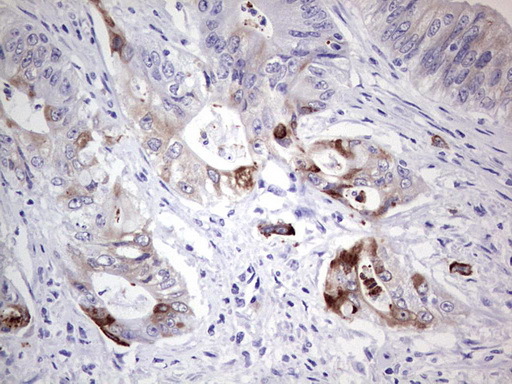

- IHC of paraffin-embedded Adenocarcinoma of Human colon tissue using anti-LAMB3 mouse monoclonal antibody. (Heat-induced epitope retrieval by 1 mM EDTA in 10mM Tris, pH8.5, 120°C for 3min).